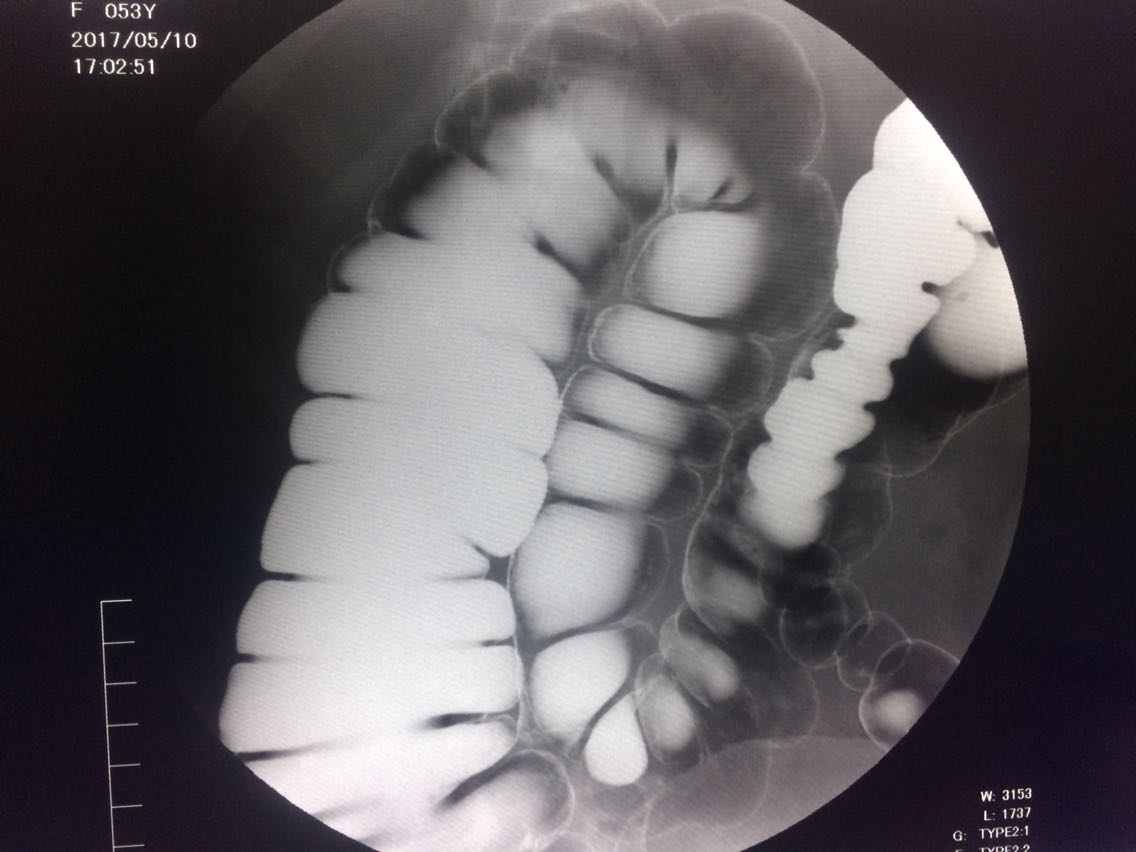

间断右下腹疼痛6年余。 6年来,无诱因出现右下腹痛,间断发生,呈胀痛,可忍受,压痛,无反跳痛。 既往:3年前,做肠镜未见明显异常。

查体,右下腹压痛。 入院做钡灌肠造影。

考虑升结肠占位。 完善术前各项检查。手术治疗。